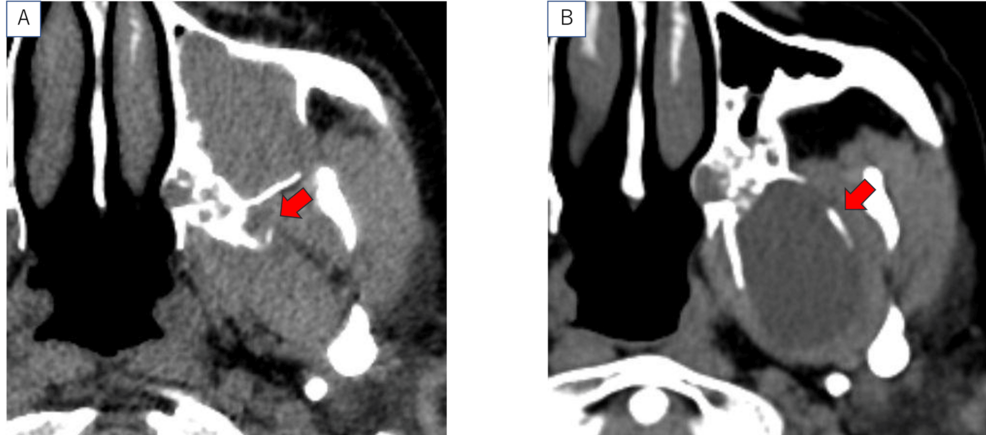

Radiomics: Extracting Insights from Medical Images

Beyond genomic data, AI is also transforming the analysis of medical images. Radiomics involves extracting quantitative features from CT scans, MRIs, and PET scans to identify patterns that are invisible to the human eye. These features can be used to predict tumor aggressiveness, treatment response, and overall survival.